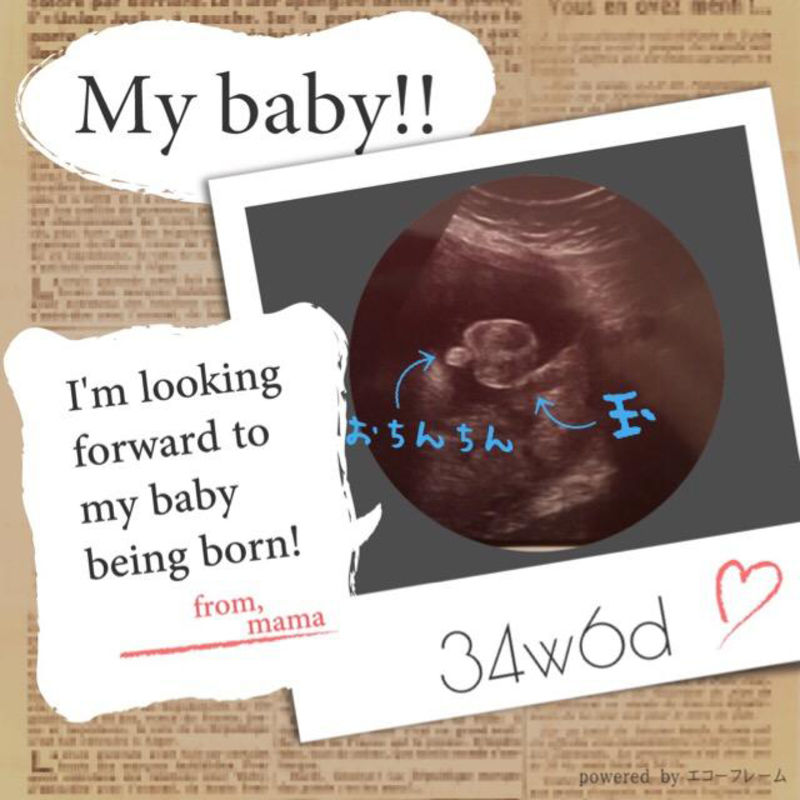

2人目が初男の子 写ったシンボルにびっくり エコー写真で振り返る妊婦生活 たまひよ

2人目が初男の子 写ったシンボルにびっくり エコー写真で振り返る妊婦生活 たまひよ